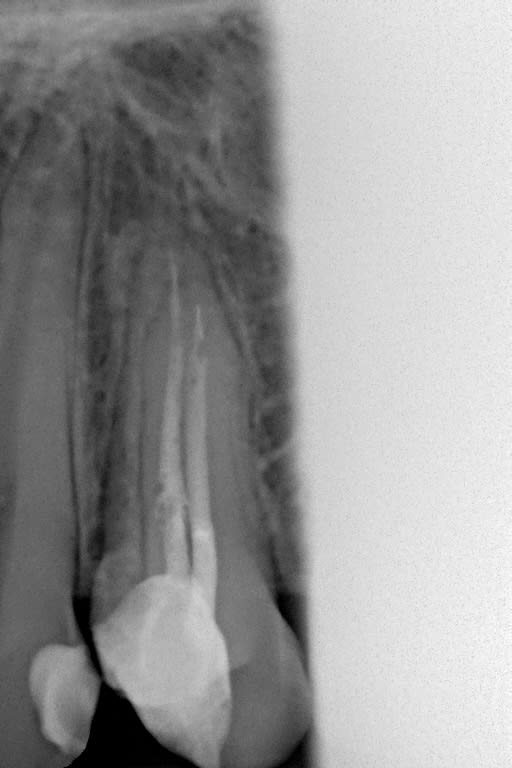

les radios

1 vdjkow - Eugenol

2 yf6iyx - Eugenol

A la vue des radios, je change d'avis. Es tu sûr qu'il y a des kystes? Demande une pano puis cone bean. Et tu vires l'endo esclusif, de toute façon.

au vue des radios je ne vois pas de faute, l'endo est pas parfaite mais loin d’être dégueu non plus

a la vue des radios ,ils sont ou les kystes ? et elles sont ou les couronnes ?

Exact, on ne voit pas de couronnes. Moi, je ne vois pas non plus de Kystes.

ce sont les radios de 2013, je n'ai pas de clichés de ce jour c'est mon correspondant qui a vu le patient